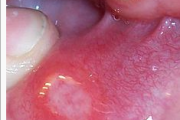

Lapse stomatiit

Tekitajad ja kliiniline pilt Gingivostomatiit – Tekitaja herpessimplex-viirus – Primaarinfektsioon, mille üldnähtudeks on palavik, halb enesetunne ja peavalu. – Herpeseville leidub põskede limaskestal, huultel ja keelel, sageli lõhkevad need kiiresti ja jätavad väikese erosiooni. – Loe edasi »